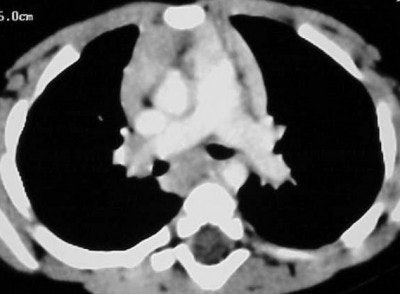

![]() |

| Figure CT 1 |

Figures CT 1 and CT 2 are 8 cc of Visipaque hand-injected into a 12-year-old girl through a 22-gauge IV with a 15-second delay. Figure 1 shows good opacification of the pulmonary arteries while figure 2 shows the abdominal aorta clearly and the spleen and liver in the arterial phases.